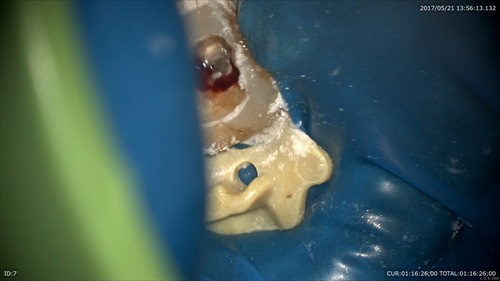

こんな状態でした。一番奥に膿の塊が見えます。歯周病と混在している病巣でぼくらの業界では治すのは難しいとされている1つの状態です。

根管から膿が。。。。